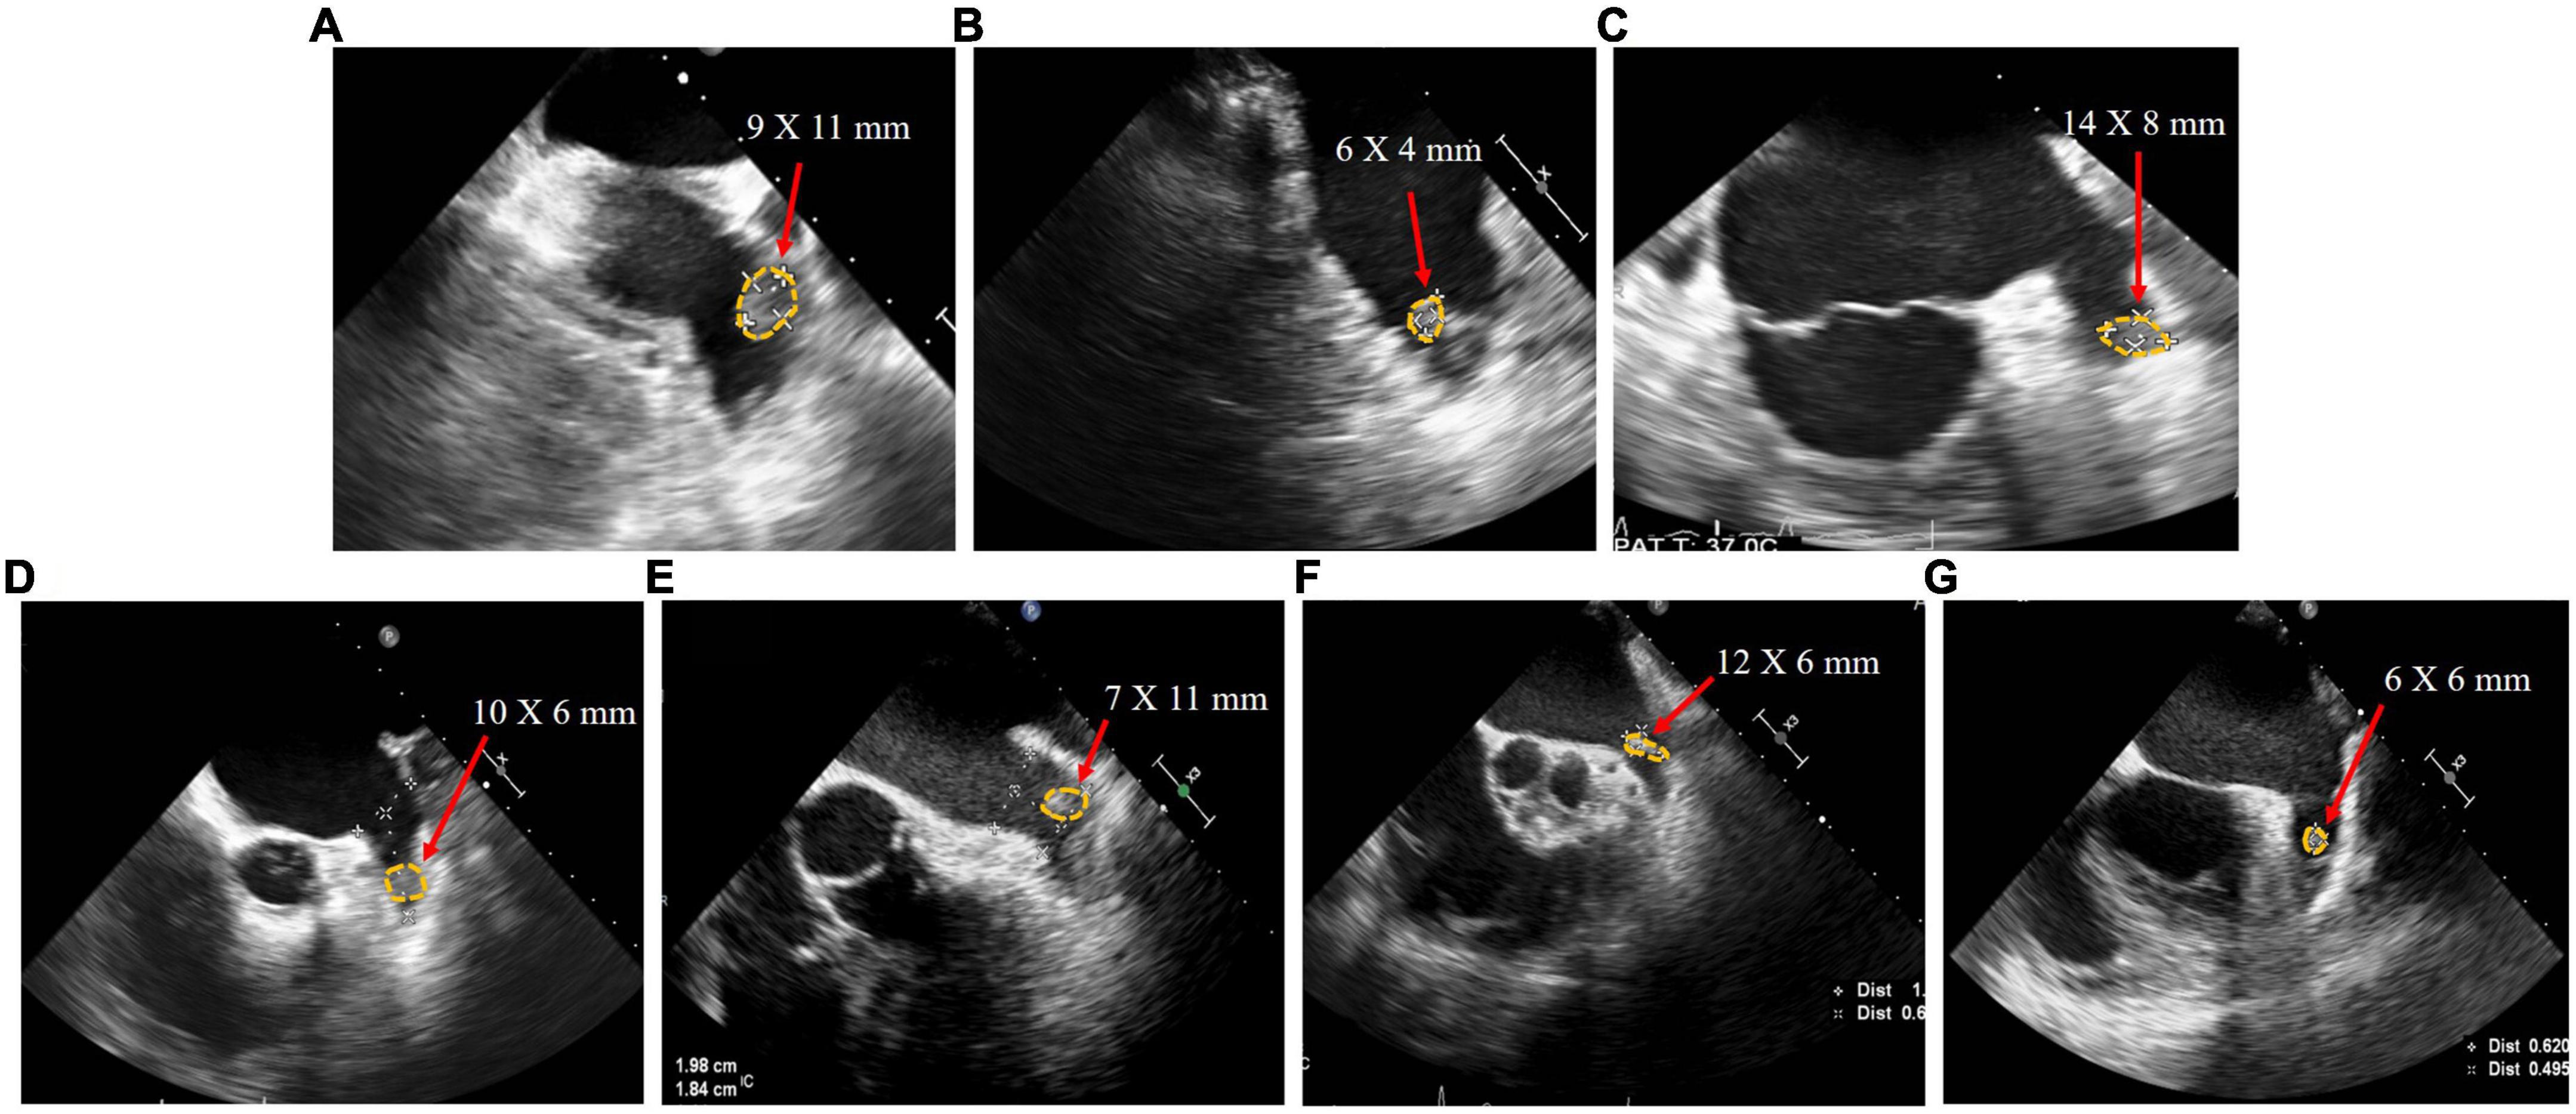

Seven patients (Patients A–G) were included in this study. Their baseline characteristics are shown in Table 1. The median age, CHA2DS2-VASc score, and HAS-BLED score of patients were 71 [53–73], 3 [2–4], and 2 [2–3], respectively. Patient B had paroxysmal AF, whereas all other patients had persistent AF. All patients who presented with persistent LAAT had received adequate anticoagulation therapy for at least 3 months after thrombus detection, involving warfarin (international normalized ratio 2.0–3.0) and standard doses of rivaroxaban according to creatinine clearance. The thrombus in Patients A, E, F, and G was located proximal to the LAA, whereas the thrombus in the other patients was located distal to the LAA (Figure 2).

Figure 2. Transesophageal echocardiography images of patient (A–G) with left atrial appendage thrombus before left atrial appendage closure.